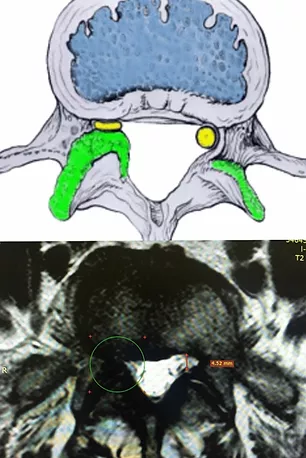

Показано схематическое изображение стеноза латерального рецессуса (на верху) и соответствующее ему МРТ-изображение (внизу). На картинке желтым цветом показан спинномозговой корешок. На МРТ видно, что грыжи у данного пациента нет, но однако, компрессия корешка есть.

Латеральный рецессус (карман) - это место где корешок отделяется от дурального мешка и направляется к межпозвонковому отверстию. Границы латерального рецессуса: латерально - ножка позвонка; вентрально - тело позвонка с вышележащим межпозвонковым диском; дорсально - верхний суставной отросток. Соответственно, при гипертрофии межпозвонкового сустава, остеофите тела позвонка или грыже диска в этой зоне происходит стеноз этой области с компрессией корешка.

Наиболее информативным методом диагностики является магнитно-резонансная томография (мощность магнита не менее 1,5 Тесла) пояснично-крестцового отдела позвоночника тонкими срезами в трех плоскостях.